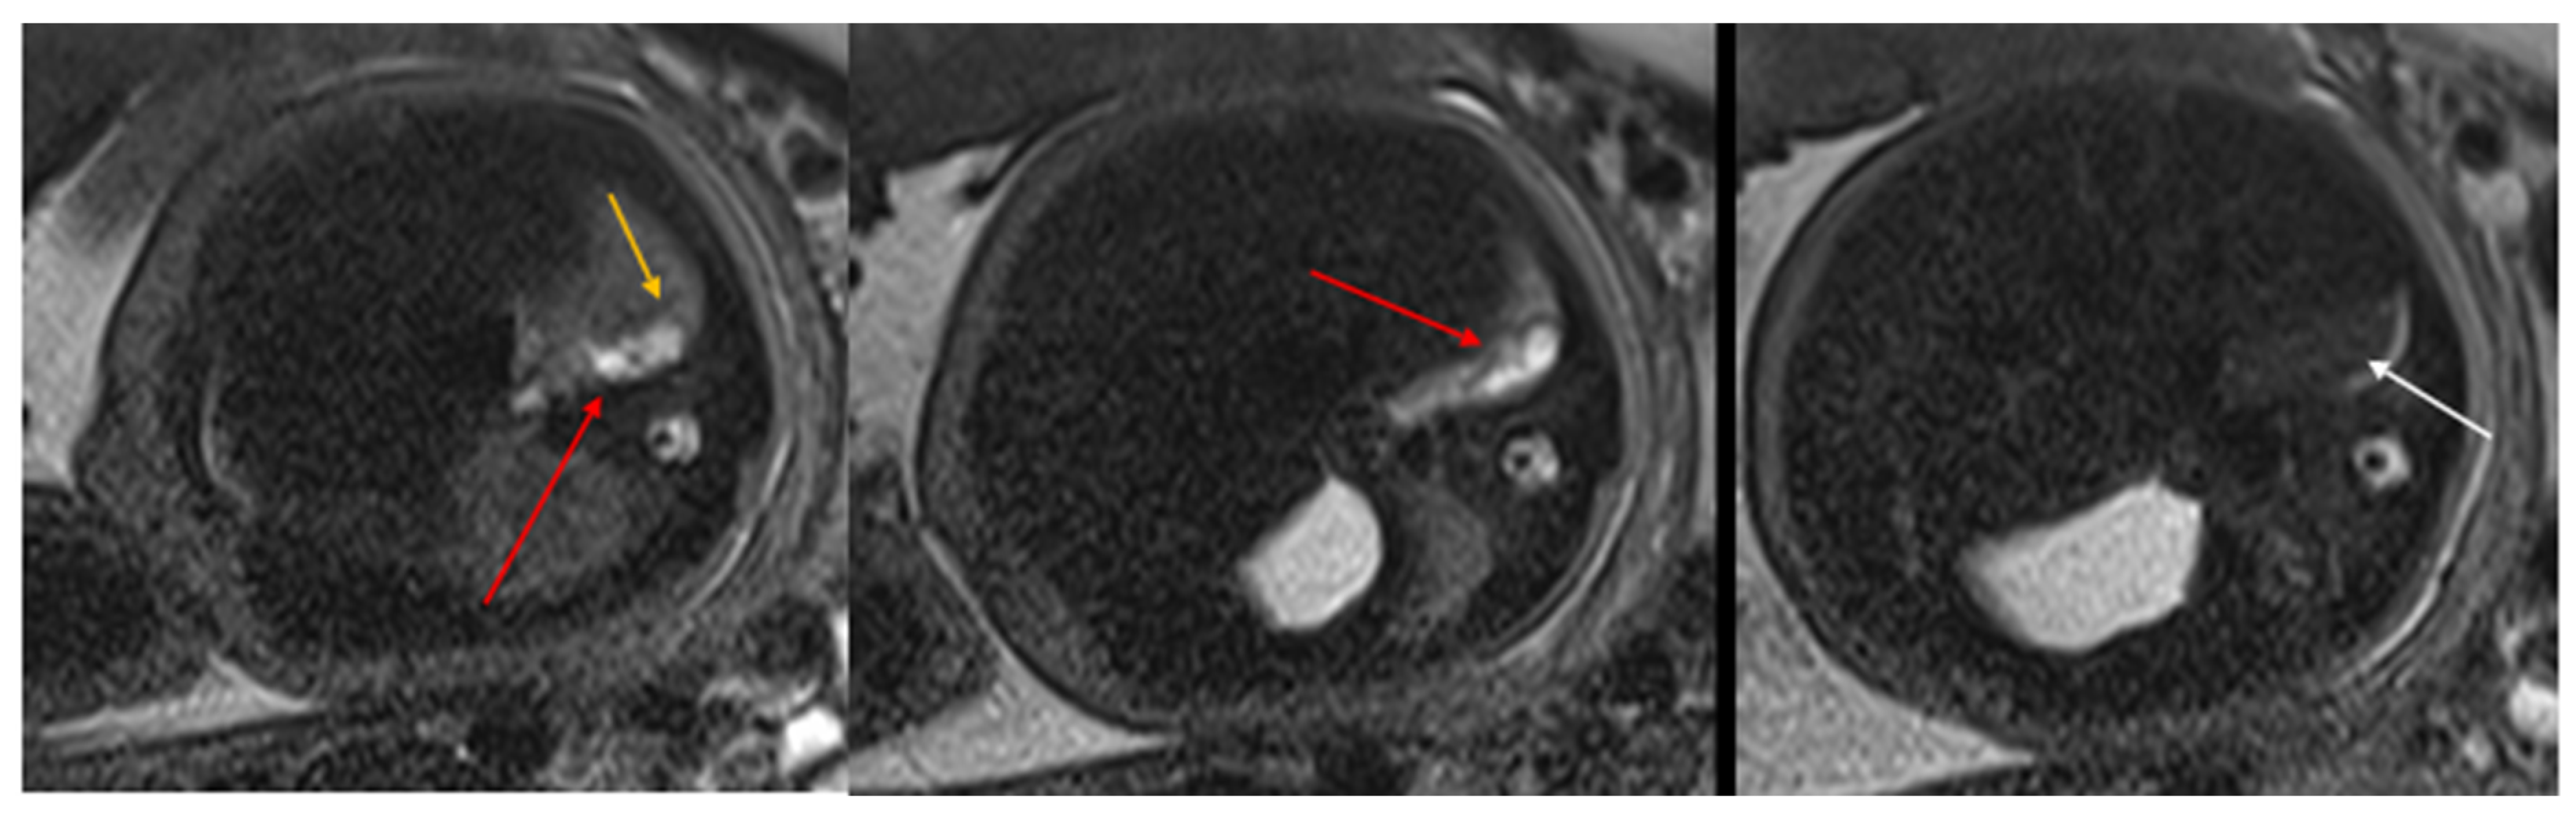

Figure 2. CPAM type II. Axial HASTE T2 MR images show a hyperintense lesion characterized by at least six cystic images (red arrow) of 2–6 mm at the lung base, with extension to the right posterior lung (orange arrow). No compression on the diaphragm or mediastinum. Minimal pleural effusion layer (white arrow).